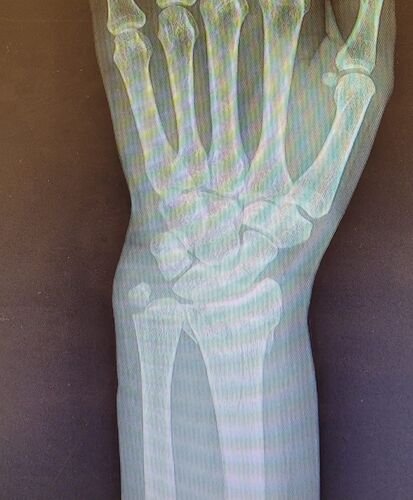

Meu nome e Isabella, mais conhecida como Snow, eu estava andando de muleta e a borracha dela saiu e eu tenho problema de equilibrio devido ao meu femur, bati o osso e piorou a situação, tive o radio do braço afetado e colocaram pino e deram um jeito de reverter porque eu ficaria com movimento do braço e mão comprometidos, tive traumatismo craniano porque bati a cabeça, esse ano eu já tinha sofrido um depois de um aparelho de raio x cair na testa mas fiquei sem sequelas na cabeça. Bom como muitos que me acompanham eu tenho uma condição rara entre mulheres que eu tenho os ossos do fêmur necrosados em mais de 75% desde 2022, eu sofri um acidente hoje andando de muleta, machuquei o fêmur, rosto, tivd que operar porque era uma emergência, não tenho muitas fotos pois estava internada mas tentei no SUS e não tinha pino de titânio,meu caso era de extrema urgência, eu to vendendo tudo e abrindo mão ate do meu apartamento pra cobrir a cirurgia e tenho ate final de setembro pra bater pelo menos 20 mil de meta, tenho inúmeras vakinhaa mostrando minha real doença autoimune e uma delas sendo rara que é osteonecrose bilateral do fêmur, o tratamento tá sendo todo particular mesmo sendo paciente do hospital das clínicas, ainda e difícil e nem sempre consigo as coisas, eu tento de todas formas é isso ainda pode me prejudicar na minha carreira, detesto pedir ajuda mas não tenho opção, a comunidade da minha área entre outros interesses sempre me apoiaram e infelizmente veio com humildade e de cabeça baixa pedir ajuda, faz tempo que tento recomeçar minha carreira desde o diagnóstico e nunca desisti dos meus sonhos e cirurgia

Vou deixar imagem atual do acidente abaixo e de algumas vakinhas anteriores